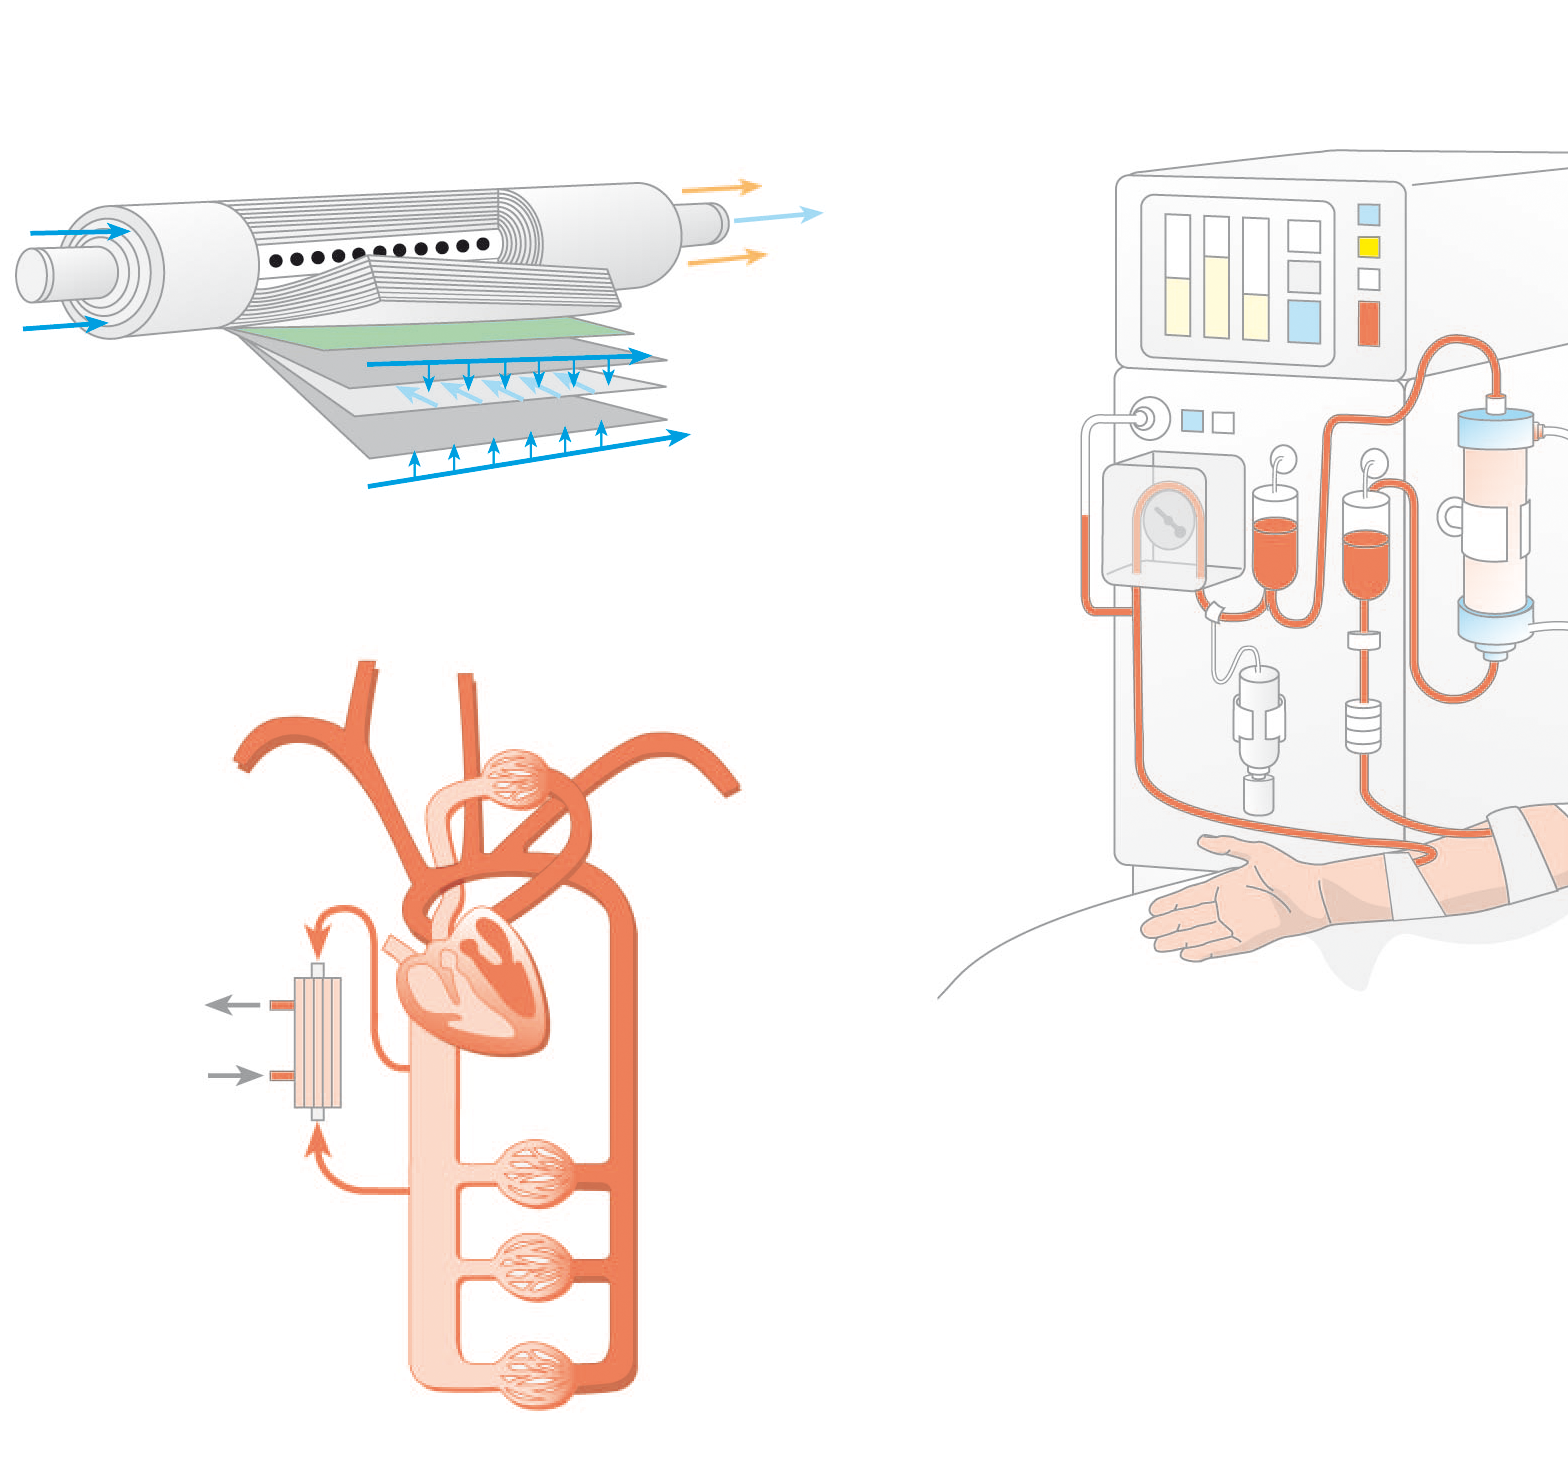

Herzlich willkommen! Ich bin Ihre Expertin für medizinische Illustrationen und kreative Kinderbuch-Illustrationen. Mit einem Auge für wissenschaftliche Genauigkeit und einer Liebe zur Gestaltung kindgerechter Erzählwelten schaffe ich Bilder, die informieren und begeistern. Entdecken Sie mein Portfolio und lassen Sie sich von meiner Arbeit überzeugen!